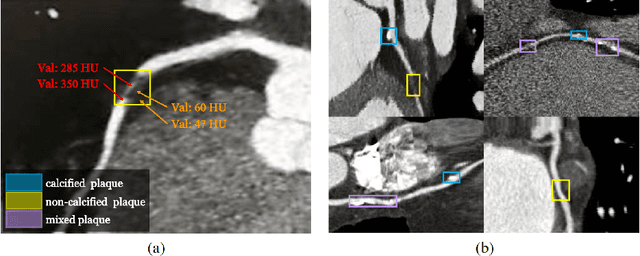

Coronary artery disease (CAD) has posed a leading threat to the lives of cardiovascular disease patients worldwide for a long time. Therefore, automated diagnosis of CAD has indispensable significance in clinical medicine. However, the complexity of coronary artery plaques that cause CAD makes the automatic detection of coronary artery stenosis in Coronary CT angiography (CCTA) a difficult task. In this paper, we propose a Transformer network (TR-Net) for the automatic detection of significant stenosis (i.e. luminal narrowing > 50%) while practically completing the computer-assisted diagnosis of CAD. The proposed TR-Net introduces a novel Transformer, and tightly combines convolutional layers and Transformer encoders, allowing their advantages to be demonstrated in the task. By analyzing semantic information sequences, TR-Net can fully understand the relationship between image information in each position of a multiplanar reformatted (MPR) image, and accurately detect significant stenosis based on both local and global information. We evaluate our TR-Net on a dataset of 76 patients from different patients annotated by experienced radiologists. Experimental results illustrate that our TR-Net has achieved better results in ACC (0.92), Spec (0.96), PPV (0.84), F1 (0.79) and MCC (0.74) indicators compared with the state-of-the-art methods. The source code is publicly available from the link (https://github.com/XinghuaMa/TR-Net).